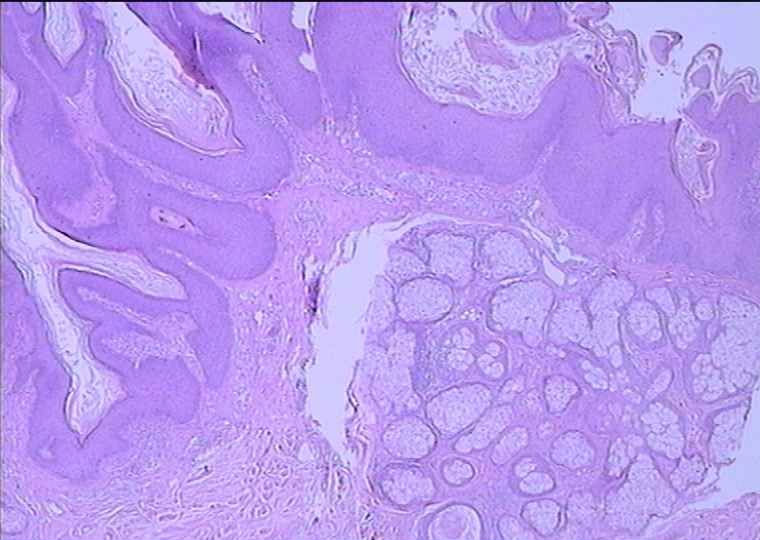

男 48岁 ,头部肿块48年(出生有),1CMX1CM,

皮脂腺痣

还是比较像皮脂腺痣。

出生就有故本例诊断皮脂腺痣

皮脂腺痣,不成熟的皮脂腺

典型皮脂腺痣!

表皮呈疣状增生,真皮内见到大量近乎成熟的皮脂腺

皮脂腺痣,表皮有增生